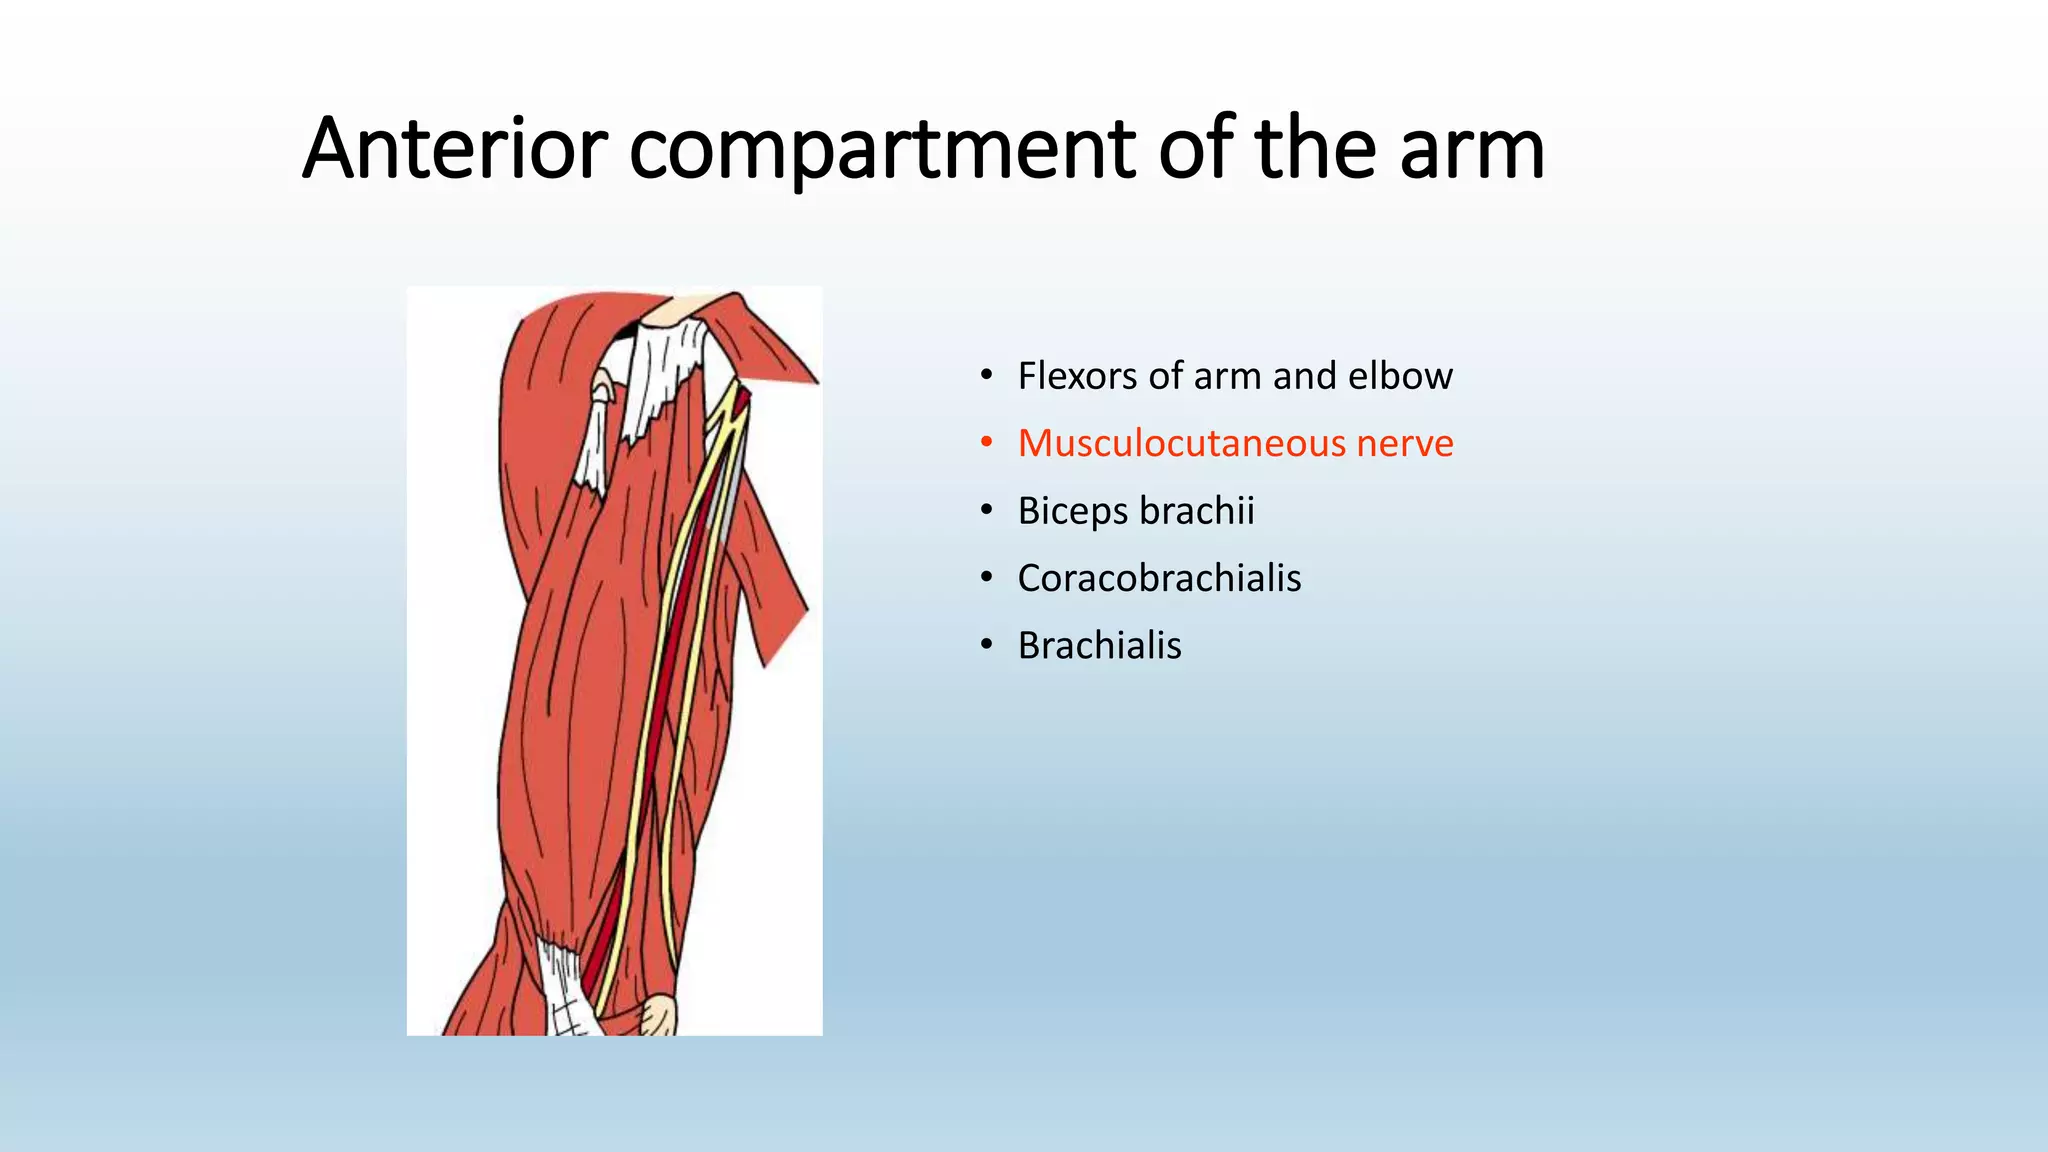

The document summarizes an anatomy revision session on the upper limb. It discusses various muscles of the upper limb including their origins, insertions, innervations and functions. Key muscles covered include the pectoralis major and minor, serratus anterior, deltoid, biceps brachii, brachialis, coracobrachialis, and triceps. It also discusses the rotator cuff muscles and muscles of the forearm including flexor carpi ulnaris and radialis. The session aims to help students identify upper limb muscles and understand their relations to nerves.